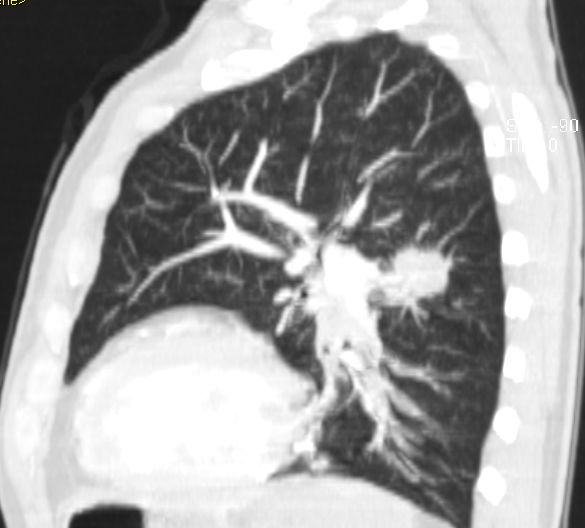

Primär zerebral metastasiertes Adenokarzinom des rechten Unterlappens. Im CT Tumor kavernenartig zerfallend. Jetzt: Sero-Pneu.

Sero-Pneu im CT